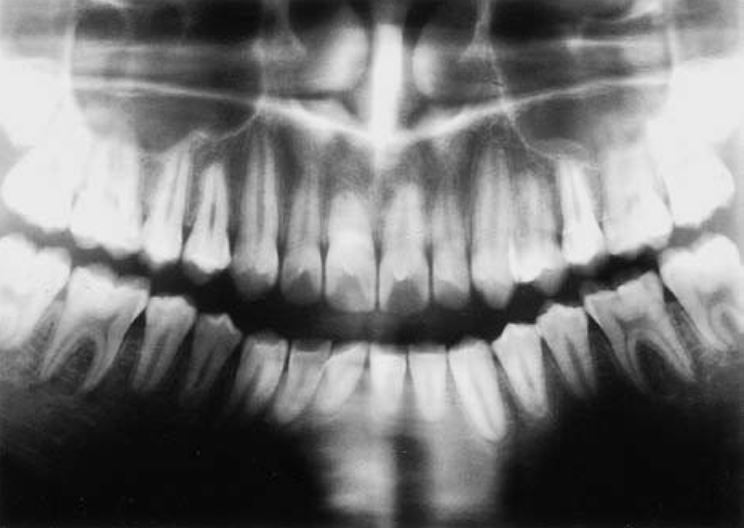

Răng bò mộng

Răng có dạng hình bò, thân răng lớn và chân răng ngắn, xảy ra trên các răng nhiều chân.

Răng có buồng tủy giãn dài, hình chữ nhật trong khi chân răng lại rất ngắn, không có điểm thắt tại đường nối men – cement. Răng vĩnh viễn bị ảnh hưởng nhiều hơn răng sữa, răng cối lớn nhiều hơn răng cối nhỏ.

Răng bò mộng thường gặp ở những bệnh nhân mắc các hội chứng di truyền như Down, Mohr, Klinefelter, ở trẻ đang điều trị ung thư.